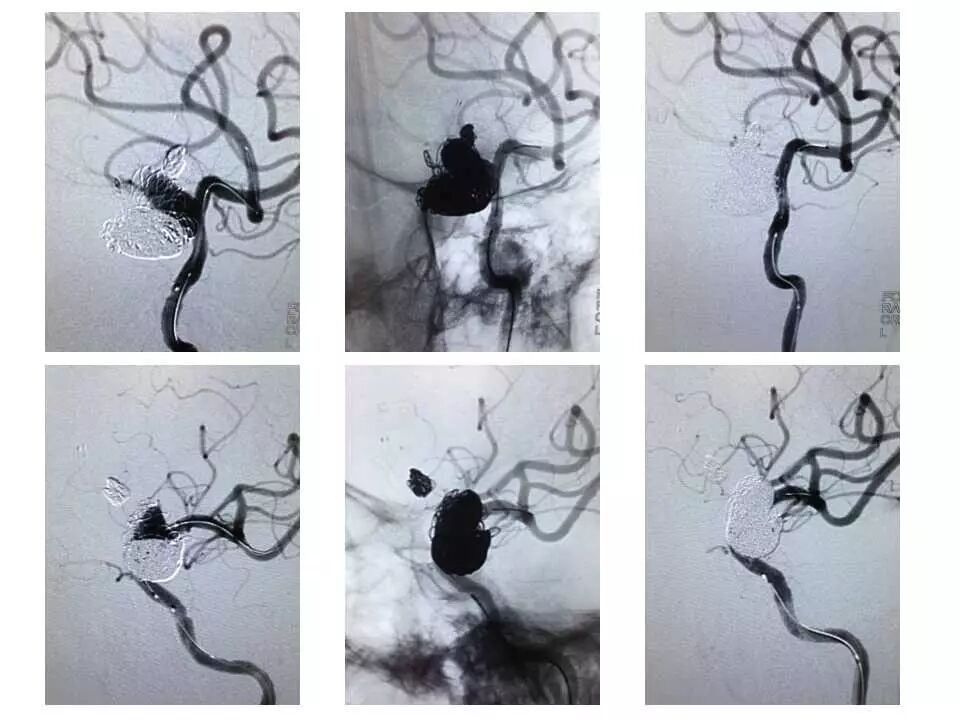

今天为大家分享的是“强生医疗CNV-神经介入专栏”第十五期,由首都医科大学宣武医院何川教授带来的“颅内动脉瘤介入治疗”精彩讲课视频及PPT,欢迎观看、阅读。文章仅代表作者个人观点,如有不同见解,欢迎同道斧正!

何川 ,首都医科大学宣武医院副主任医师,中国医师协会神经介入专业委员会常务委员,长期从事脑血管病和脊髓血管病的手术及介入治疗和相关研究工作。首都医科大学神经外科博士,师从于中国神经介入开创人凌锋教授;日本东北大学医院脑血管病治疗科博士后,师从于日本国脑血管病血管内治疗的开创者高桥教授。